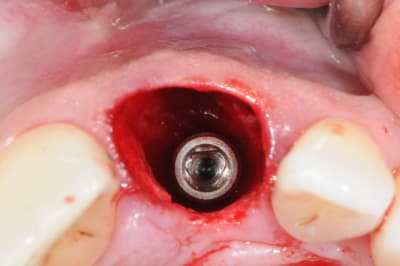

Une extraction avec mise en charge immédiate qui ne c'est pas bien passée (mauvaise ostéo-intégration), donc dépose (4x140mm) et repose d'un 4.6x140, et ROG car pas d'os vestibulaire.

MP3 (OstéoBiol) et membrane évolution std 30x30mm (OstéoBiol)

Produit sympa qui ne laisse pas de particule comme le BioOss.

Pas de pin ou vis, seulement sutures.